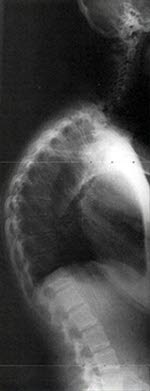

Den typiske krumningen av ryggen til en tenåring gir mistanke om tilstanden. Ofte foreligger også økt stivhet i ryggen, der ungdommen ikke klarer å bøye seg like langt fremover som andre og der det samtidig strammer i musklene på baksiden av lårene. Sykdommen vises på røntgenbilder, hvor de karakteristiske kileforandringene av ryggvirvlene kan ses. Bakgrunnen for å ta et slikt røntgenbilde er vanligvis en sykehistorie med ryggsmerter hos en tenåring med forandringer av ryggens krumning.